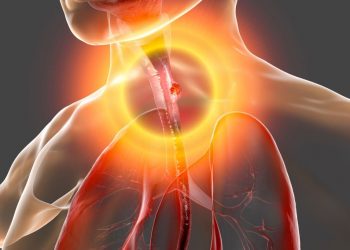

Four Disorders That Cause Dysphagia

Dysphagia can be divided into two main categories: esophageal dysphagia and oropharyngeal dysphagia. The former occurs when food gets stuck...